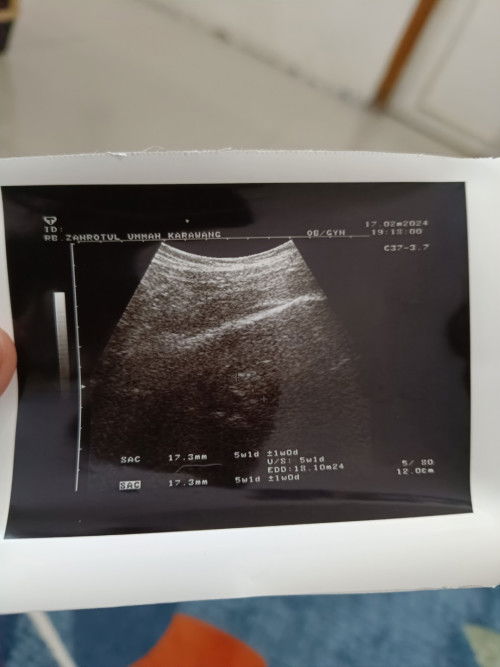

Ciri ciri janin tidak berkembang

Pas usia 6 minggu di USG blm kliatan. Terus saya d suruh balik 2 minggu lg. Barusan saya USG lg d usia 8w2d Tp hasilnya blm jls. Janin masih kecil. Dan d hasil usgnya usia kehamilan baru 5w1d. Dan kata bu bidannya, klo seandainya janinku tdk berkembang nanti akan memberi sinyal, misal flek atau kluar darah. Tp Alhamdulillah sampai saat ini aku tdk ada flek, dan aku juga merasakan perubahan di badan aku. Kya PD membesar, perut membesar. Mnurut bunda bunda semua gimna ya, adakah yg sma?